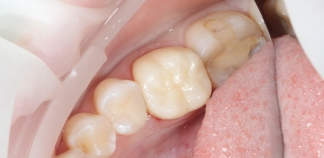

До лечения

Жалобы на эстетику зубов.

Пациенту 46 лет.

Как лечили

Проведено препарирование четвертого и пятого зуба с последующей фиксацией постоянных коронок.

Лечение проведено в течение одной недели.